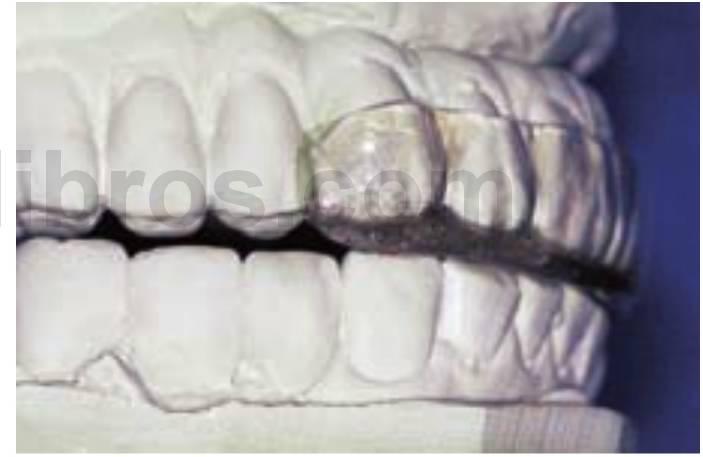

Afortunadamente, existen muchos signos clínicos que avisan de un excesivo rechinamiento. Los signos del bruxismo incluyen un aumento del tamaño de los músculos masetero y temporal (estos músculos y el pterigoideo externo pueden presentar molestias), desviación del maxilar inferior en la apertura, disminución de la apertura oclusal, aumento de la movilidad dentaria, desgaste cervical de los dientes, fractura dentaria o de las restauraciones y descementado de coronas o de prótesis fija. Sin embargo, el método de diagnóstico mejor y más sencillo del bruxismo es el examen del desgaste dentario. No solo es la forma más fácil de determinar el bruxismo en cada paciente individual, sino que permite, además, clasificar esta patología en ausente, suave, moderada y grave (figs. 6-1 a 6-3). Si no existen patrones de desgaste anterior denota una ausencia de bruxismo. En el bruxismo suave aparece un ligero desgaste en dientes anteriores sin que exista un compromiso estético. El bruxismo moderado conlleva facetas de desgaste incisales obvias, pero no hay un patrón de desgaste oclusal posterior. En el bruxismo grave desaparece la guía anterior por el excesivo desgaste y, además, el desgaste dentario posterior es obvio.

A menudo, los pacientes bruxistas repiten movimientos mandibulares, diferentes a los movimientos bordeantes, y tienen una determinada dirección. Como resultado, el desgaste oclusal es muy específico y principalmente en un solo lado de la arcada, o incluso, en solo unos dientes (fig. 6-4).